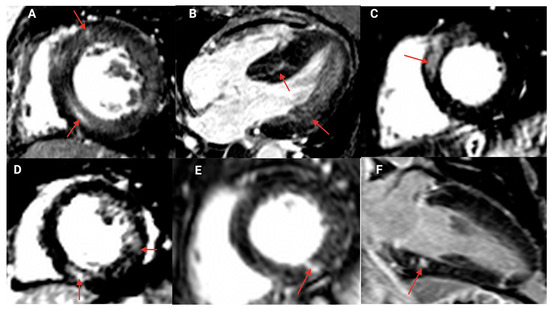

3.3. Late Gadolinium Enhancement

| LGE, n/contrast study, n (%) | 52/69 (75) | 8/18 (44) | 44/51 (86) | <0.001 |

| Ischemic pattern | 11/69 (16) | 0 (0) | 11/51 (22) | |

| Nonischemic pattern | 41/69 (59) | 8/18 (44) | 33/51 (65) |

| n = 52 (%) | |

|---|---|

| 11 (21.2) |

| Subendocardial with microvascular obstruction | 1 (1.9) |

| Transmural | 1 (1.9) |

| Transmural, mid wall, and right ventricular insertion point | 1 (1.9) |

| Transmural and right ventricular insertion point | 1 (1.9) |

| Transmural with microvascular obstruction | 5 (9.6) |

| Transmural and subendocardial | 1 (1.9) |

| Focal transmural and right ventricular insertion point | 1 (1.9) |

| 41 (78.8) |

| Right ventricular insertion point | 13 (25) |

| Focal and right ventricular insertion point | 1 (1.9) |

| Mid wall and right ventricular insertion point | 17 (32.7) |

| Patchy mid wall | 7 (13.5) |

| Focal, mid wall, and right ventricular insertion point | 1 (1.9) |

| Subepicardial, mid wall, and right ventricular insertion point | 1 (1.9) |

| Subepicardial | 1 (1.9) |